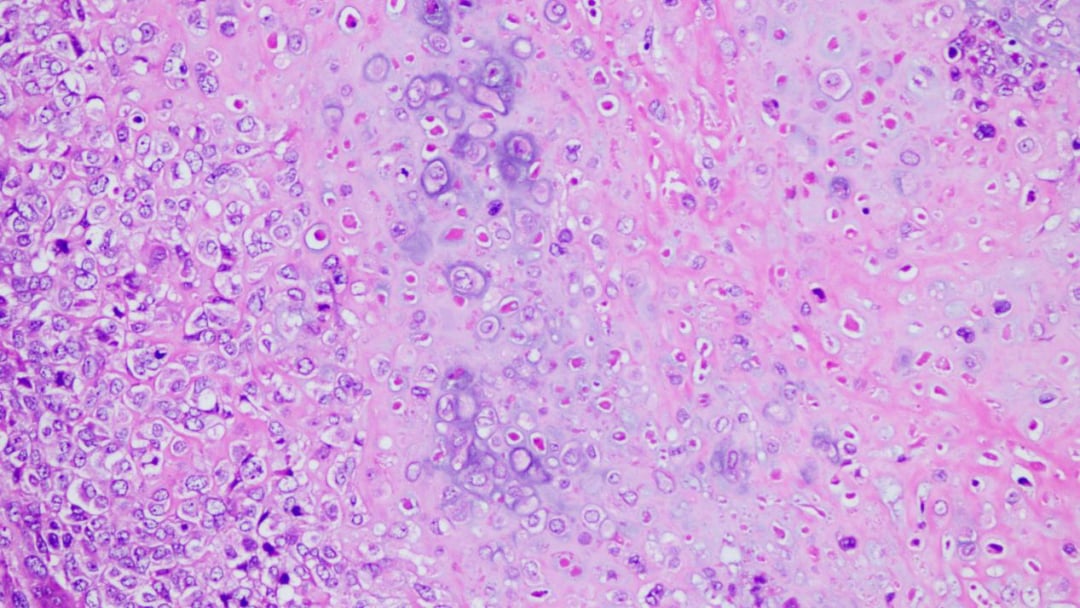

- 细胞形态多样:肿瘤组织由多种形态的细胞构成。大部分区域由交织分布的梭形细胞组成,呈现出纤维肉瘤样的外观;部分区域则呈现血管外皮瘤样结构;还有少部分卵圆形细胞围绕在骨样和软骨样基质周围。

- 高度恶性特征:肿瘤细胞表现出高度的异型性,细胞大小不一,核深染,形态怪异。病理性的核分裂象(癌细胞分裂的标志)随处可见,这预示着肿瘤具有很强的增殖和侵袭能力。

- 关键诊断依据:最关键的发现是肿瘤组织中产生了花边状的骨样组织和软骨样基质,这是诊断骨肉瘤的决定性证据。此外,组织中还散在分布着破骨样多核巨细胞。

低倍镜下肿瘤疏密区相间

中倍镜下,肿瘤大部分区域呈梭形细胞纤维肉瘤样形态

中倍镜下可见花边状骨样组织

中倍镜下可见软骨样瘤组织

高倍镜下,可见骨样组织及破骨样多核巨细胞

高倍镜下,肿瘤细胞高度异型性,可见多个病理性核分裂象